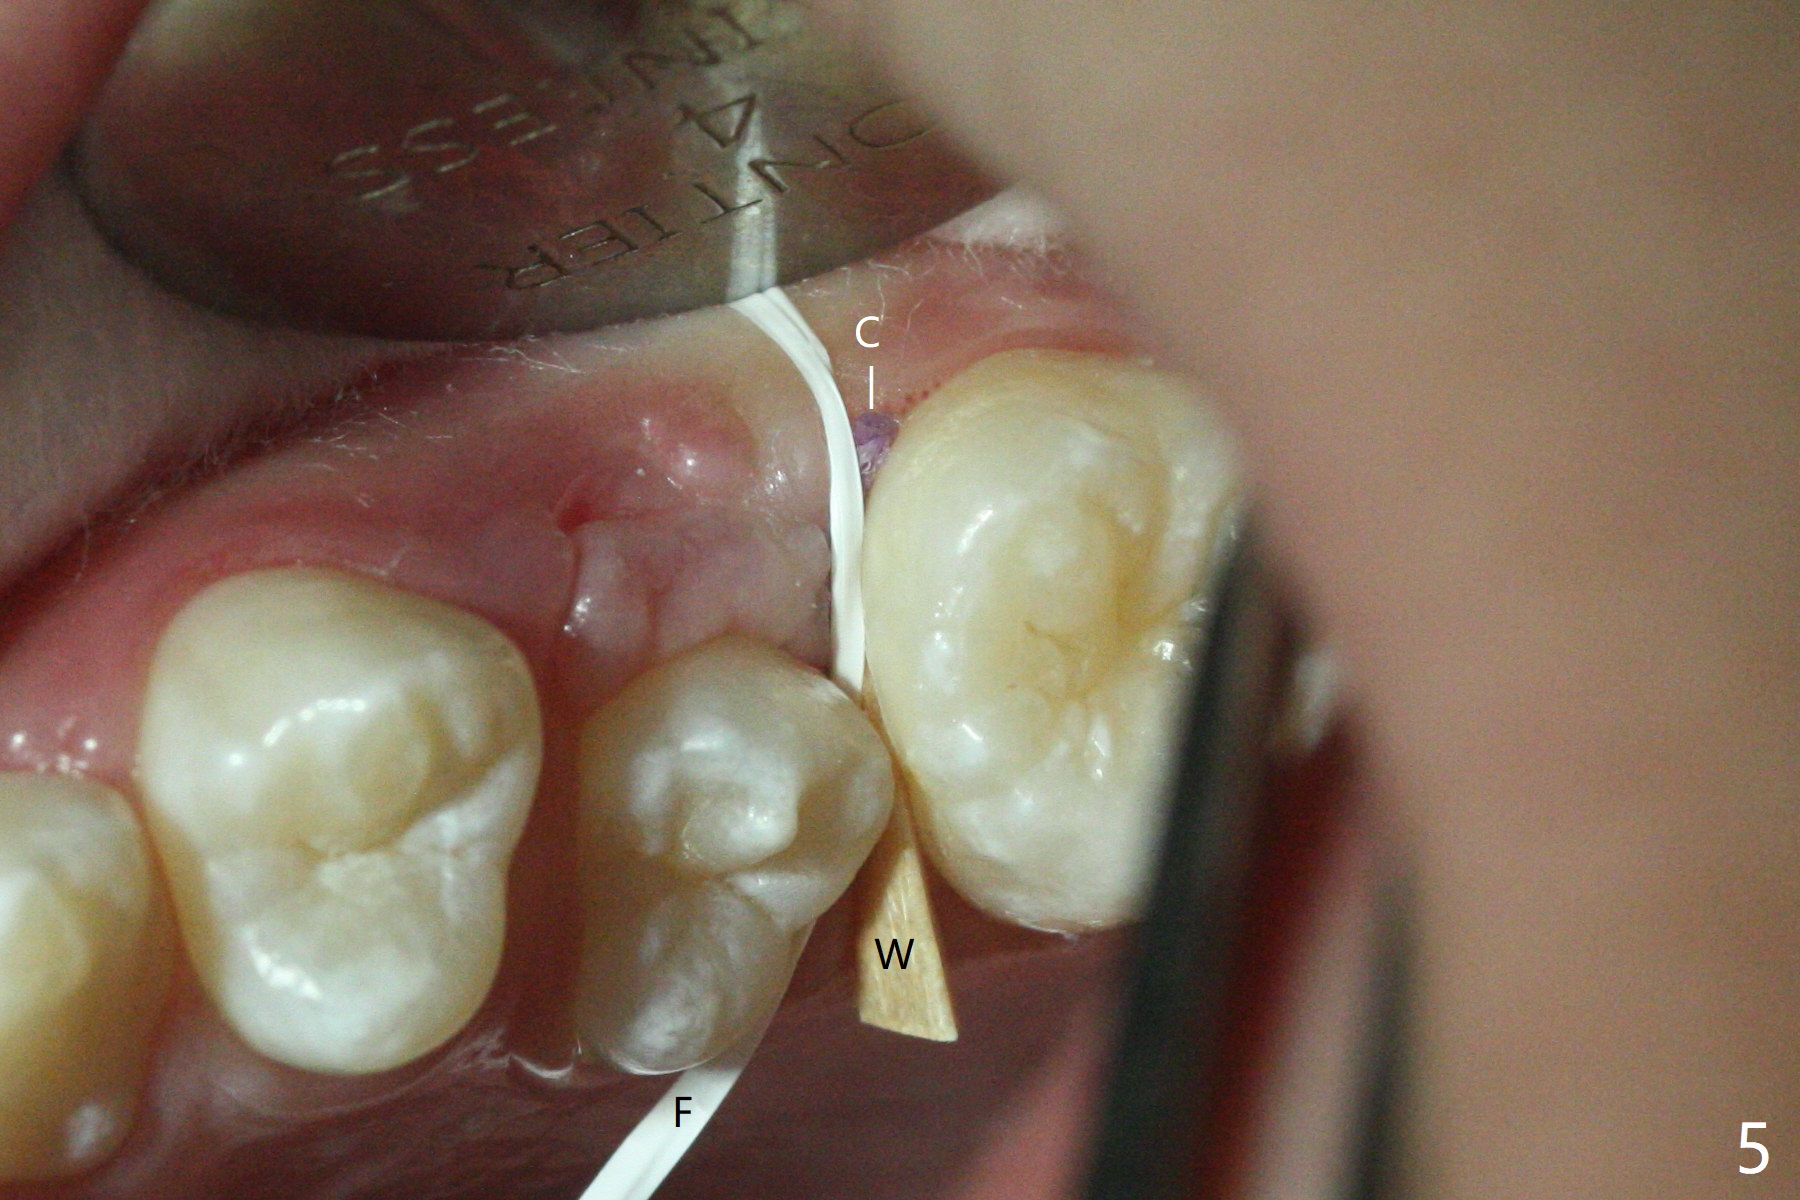

10岁半女孩上颌第二乳磨牙远中龋好像造成第一恒磨牙近中龋(图一)。要求妈妈当乳磨牙脱落时,带她回来补牙。由于新冠病毒,女孩1年3个月后才回来,右上第二前磨牙已经基本完成萌出,右上6近中龋被掩盖了(图二),而左侧前磨牙腭侧部分萌出(图三,四),磨牙近中龋(表现为脱钙,图四:箭头)正好暴露。塞入gingival retraction cord(图五:C)和wedge (W),去龋,填入树脂,两牙之间通过牙线(F),光固化。之后不需要抛光。